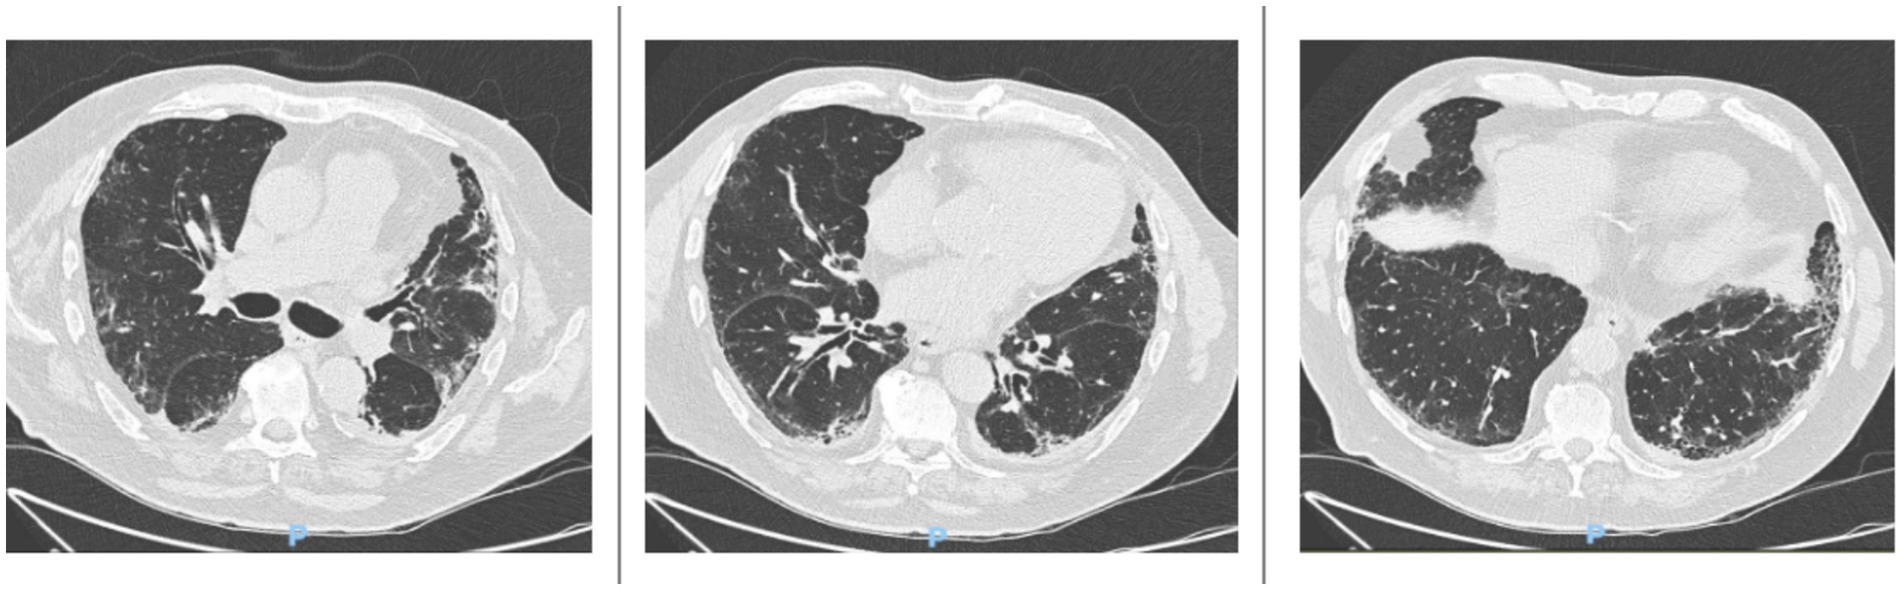

In November 2024, an HRCT scan showed mild disease progression, with increased traction bronchiolectasis in the anterobasal and laterobasal segments of the left lower lobe, the anterior segment of the upper lobe, and the apical segment of the right lower lobe (Figure 2).

Figure 2

HRCT scans taken in November 2024 reveal a mild progression of interstitial lung disease (ILD). There is a slight increase in traction bronchiolectasis, which is more pronounced in the anterobasal and laterobasal segments of the left lower lobe, the anterior segment of the upper lobe, and the apical segment of the right lower lobe.